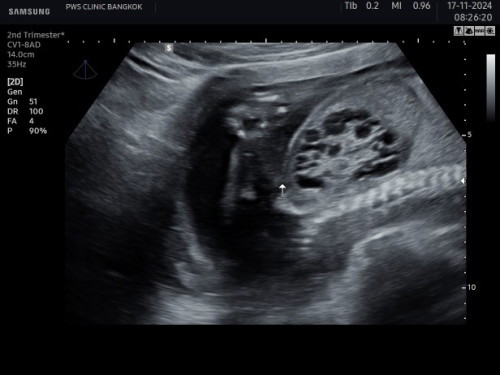

ขออนุญาตถามแม่ๆนะคะคือพอดีว่าแม่เพิ่งไปอัลตร้าซาวด์4Dที่คลินิกมาแล้วคุณหมออัลตร้าซาวด์เจอถุงน้ำในไตของน้องแล้วคุณหมอบอกว่าถ้าในอนาคตไตข้างที่พบถุงน้ำอาจจะใช้งานไม่ได้แล้วน้องจะมีไตแค่ข้างเดียวแต่ยังใช้งานได้และยังดำรงชีวิตอยู่ได้ปกติมีแม่คนไหนเคยมีลูกเป็นเหมือนน้องไหมคะอยากขอคำปรึกษาหน่อยหรือแม่ๆคนไหนพอจะมีข้อมูลที่ทราบอยู่ขอคำแนะนำให้แม่หน่อยค่ะเพราะว่าแม่กังวลใจมากและสงสารลูกมากๆค่ะที่จะต้องเกิดมามีโรคประจำตัวขอขอบคุณคำแนะนำล่วงหน้านะคะ🙏🏻🥹🥺 ##ขอคำแนะนำกับแม่ๆด้วยนะคะ